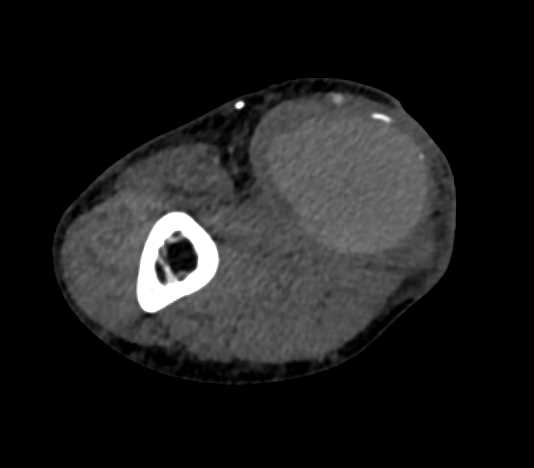

Cirrhosis with Portal Hypertension and Varices and Splenomegaly